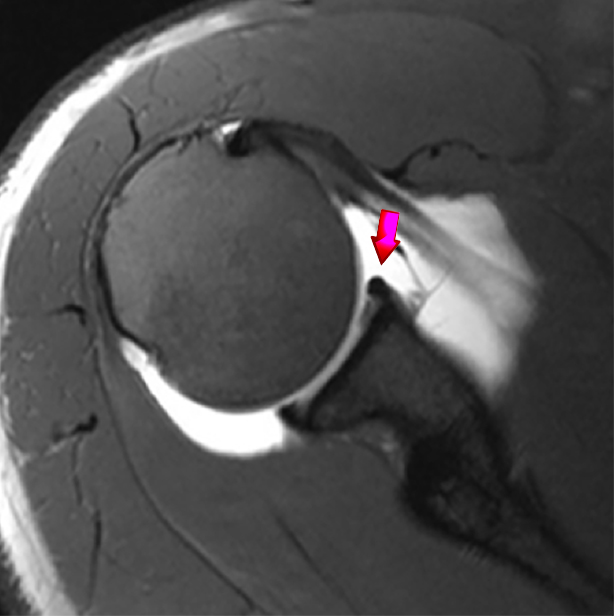

MRI-Normal-labrum-Dr-sujit-Jos

Shoulder Dislocation

badminton-jump-smash-shoulder-dislocation MRI-Labral-tear-shoulder-dislocation-dr-Sujit-Jos Bookmark the permalink.